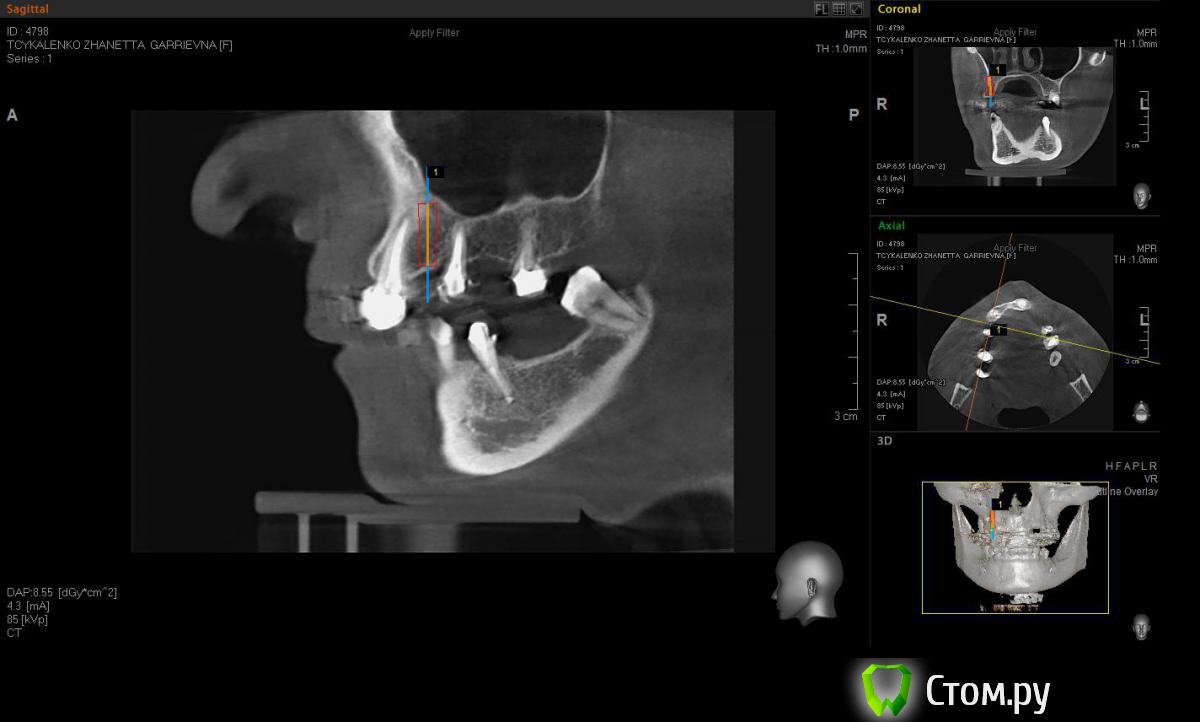

Евгений Ходыкин Опубликовано 20 мая, 2014 Автор Поделиться Опубликовано 20 мая, 2014 Замерил... Ссылка на комментарий

АнтонТЛТ Опубликовано 20 мая, 2014 Поделиться Опубликовано 20 мая, 2014 А теперь замерьте угол в районе 15 зуба через фиссуру Ссылка на комментарий

Евгений Ходыкин Опубликовано 20 мая, 2014 Автор Поделиться Опубликовано 20 мая, 2014 Ну как-то так. Сути не уловил) Свой зуб стоит совсем иначе, да и ширина гребня иная совсем... Ссылка на комментарий

АнтонТЛТ Опубликовано 20 мая, 2014 Поделиться Опубликовано 20 мая, 2014 Суть в том, что изначально не правильно угол замерили 1 Ссылка на комментарий

Евгений Ходыкин Опубликовано 20 мая, 2014 Автор Поделиться Опубликовано 20 мая, 2014 Суть в том, что изначально не правильно угол замерилиДак изначально я замерил строго по гребню, в условиях наибольшей ширины гребня, там угол под 30 и выходил. При ангуляции как у 1.5 у меня и получается дефицит кости, что примерно изобразил на схеме постановки имплантата. Поправьте, если не прав... Ссылка на комментарий